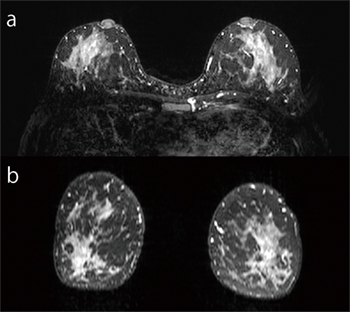

isoFSEでは,refocusパルスのフリップ角を制御することで信号減衰を抑制し,長いエコートレインでも信号を得ることができ,高速3D撮像が可能である。本手法に,B1不均一性の影響を受けにくい「H-sinc」(選択的脂肪抑制法)を用いることにより,広範囲の脂肪抑制画像を得ることが可能である(図1)。

図1 H-sinc併用3D T2強調画像

a:元画像

b:MPR画像

1.1mm×1.1mm×2(1)mm reso,

164slice,3min4s